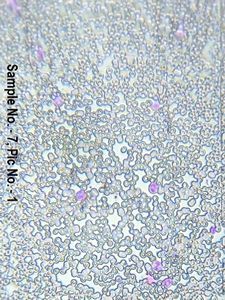

Blood Smear Stained with Leishman Stain Under Foldscope

Applause Icon140x Magnification